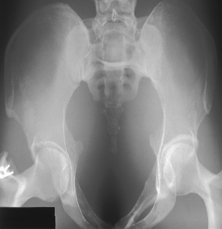

For AP and “frog-leg” laterals of the hips, specially shaped ovarian shields can be carefully placed over the area of the ovaries without obscuring essential anatomy as shown. This should be done on all female children and adults of childbearing age. These ovarian shields, however, may obscure essential anatomy on certain pelvic examinations. Departmental policy regarding shielding and kV range to be used should be determined.